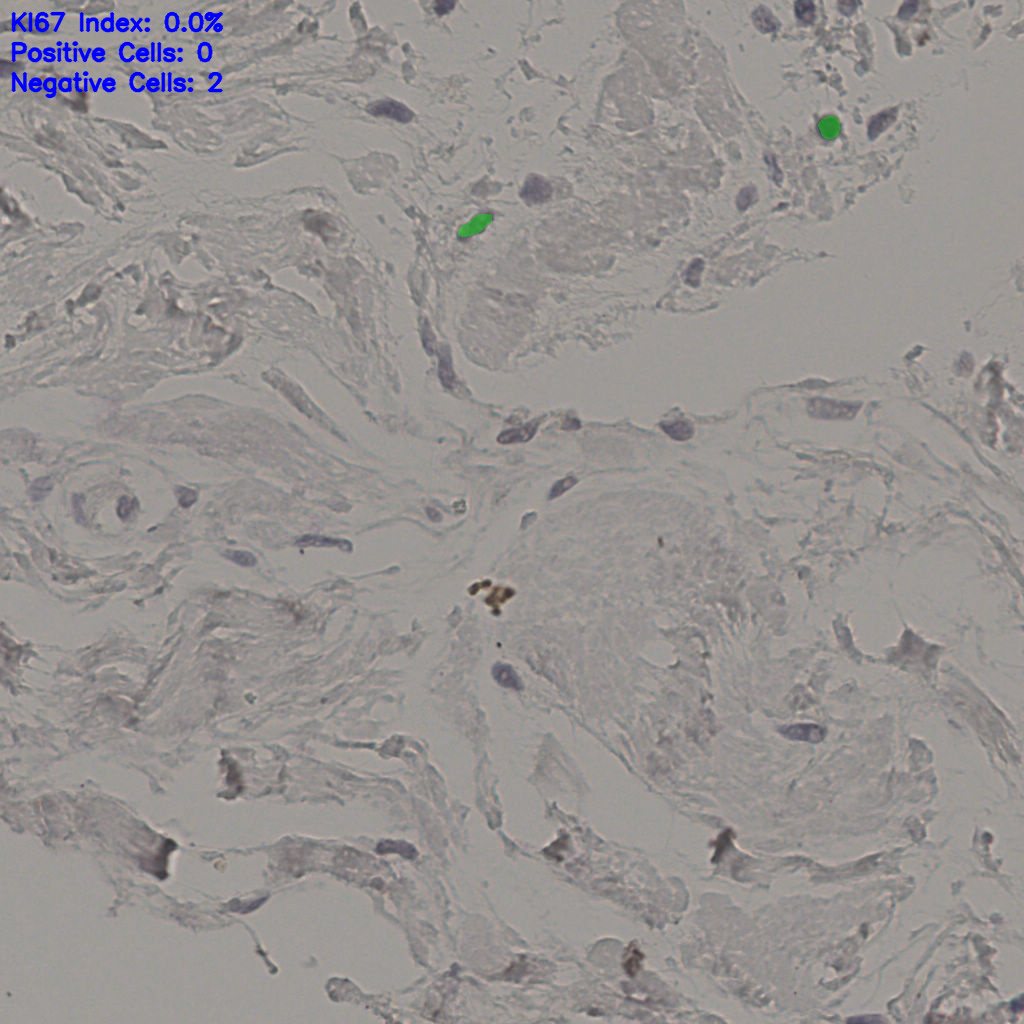

17.75%

Ki67 指数

阴 7986

阳 1723

切片统计

总切片

2640

有效

412

已标记

有效率

16%